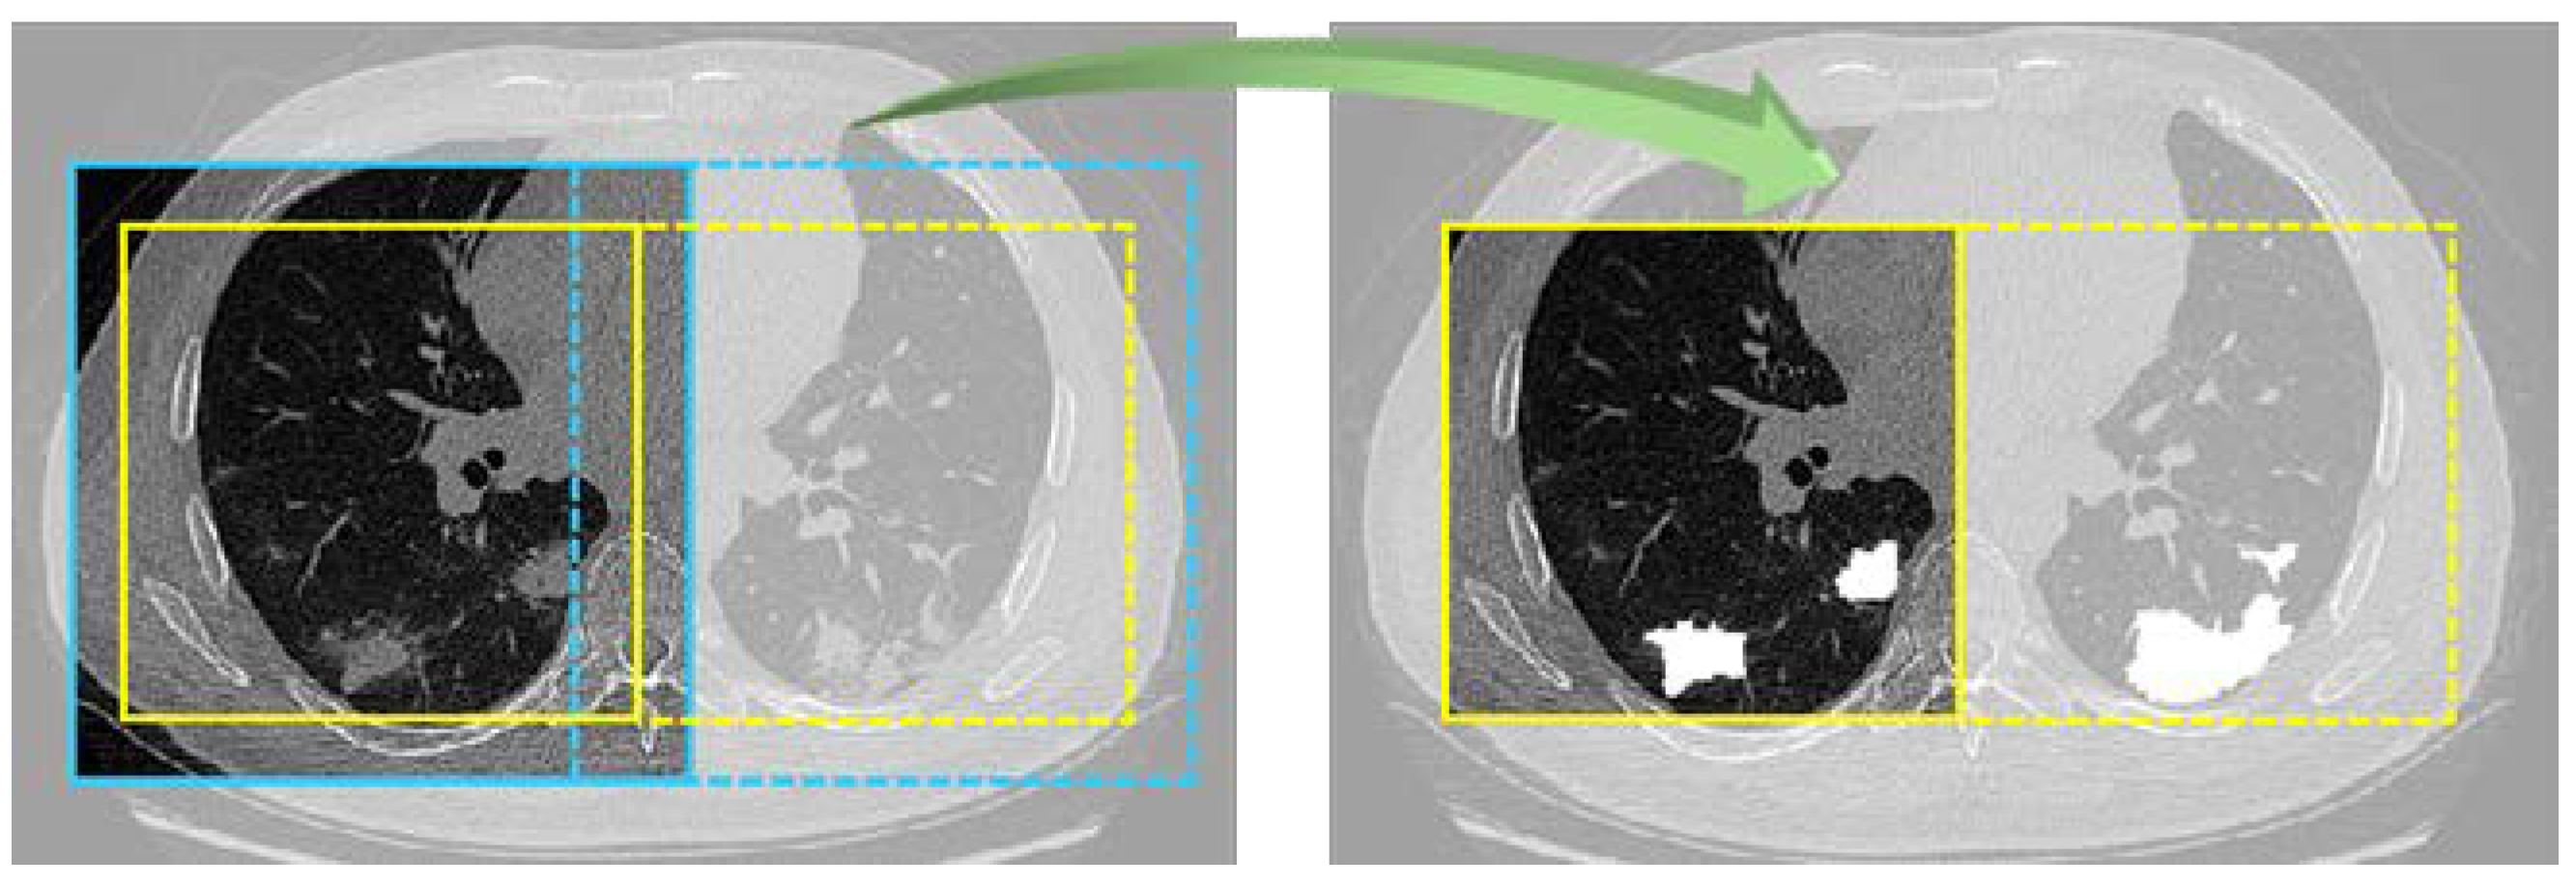

In initialization stage, experiment parameters were set as: small batch of 12 samples, Adam optimizer [37], batch normalization, deep supervision [38], and 100 epochs. To prevent memory congestion, data were randomly cropped into slices with a size of 128 × 128 × 128 in each step, and the current batch of data were read only. In testing progress, testing data were cyclically cropped until the entire data were traversed, and finally the complete splicing of data was realized. In addition, the overlap-tile [39] strategy was adopted: by intercepting yellow line area as actual segmentation result (Figure 5), possible splicing errors were explicitly ignored. The segmentation threshold was set as 0.5.

Figure 5.

Overlap-tile strategy. Blue line area is output area. Through the instructions of the green 3D arrow, the actual reserved output is yellow line area.